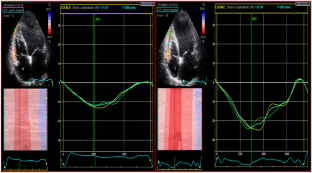

Fig. 2